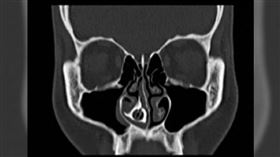

她「鼻水流10年」治不好!醫一挖:化石?

這真的太扯了!鼻涕流了10年竟然不是感冒?大陸杭州一...